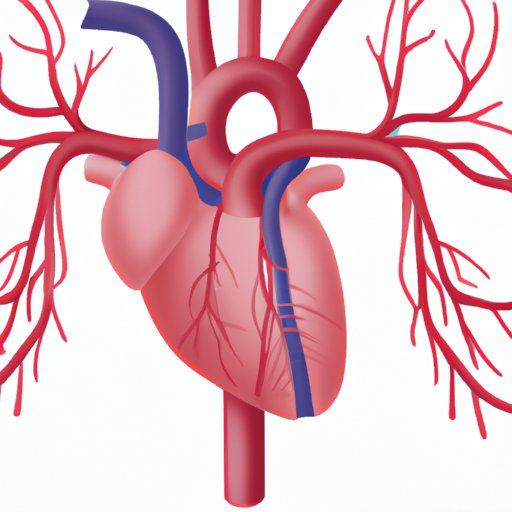

Understanding the vessels that carry deoxygenated blood and how they contribute to the cardiovascular system’s overall health is crucial. This article explores the five types of deoxygenated blood vessels, their interplay with other components of the circulatory system, and how they function in the body.

Which Artery Carries Deoxygenated Blood: Understanding the Deoxygenated Pathway and the Importance of the Deoxygenated Artery

This article explains the deoxygenated pathway and its artery, the significance of maintaining good cardiovascular health, and the pathway of blood flow. It highlights the importance of understanding the circulatory system and the role of the deoxygenated pathway in maintaining the body’s function.

The Pulmonary Trunk: Understanding the Heart’s Connection to the Lungs

The pulmonary trunk plays a vital role in regulating the amount of oxygenated blood in the body. This article will explore everything you need to know about the heart’s connection to the lungs, with a focus on the anatomy of the heart, the function of the pulmonary trunk and its connection to the right ventricle, and common issues associated with the pulmonary trunk.